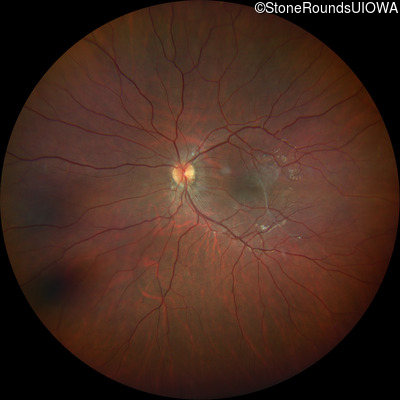

This 9 year old male was noted to have some crossing of his eyes at 2 months of age and the eye exam which followed identified a retinal lesion in the right eye. When he was six years old an epiretinal membrane was noted in his left eye. Two years later it was decided that it was a thin hamartoma in that eye as well. He underwent neuroimaging at age 7 which identified bilateral acoustic neuromas.